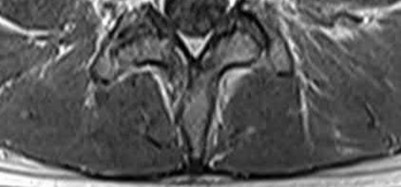

Figures 9a through 9c are the MRI scans of a 65-year-old woman on dialysis who has thoracic back pain, malaise, and an elevated erythrocyte sedimentation rate (ESR). The clinical history and imaging findings are most consistent with

Corrent answer: 3

The sagittal MRI scans are pathognomonic for diskitis and osteomyelitis with fluid signal and destructive changes in the disk on T2 (Figure 9a), low signal with blurring of the disk margins on T1 (Figure 9b), and on the T1 gadolinium image (Figure 9c) vertebral body enhancement on either side of the affected disk with dark signals within the disk corresponding to the bright fluid signal from the T2 image. Metastatic carcinoma tends to affect the vertebral body with relative disk sparing, and lymphoma can affect the vertebral body but often has soft tissue extending within the spinal canal. Osteoporotic fractures are contained with the vertebral body. Renal osteodystrophy can result in a diskitis picture with disk destruction but one would not expect an elevated ESR or malaise, and this is much rarer than diskitis in dialysis patients.